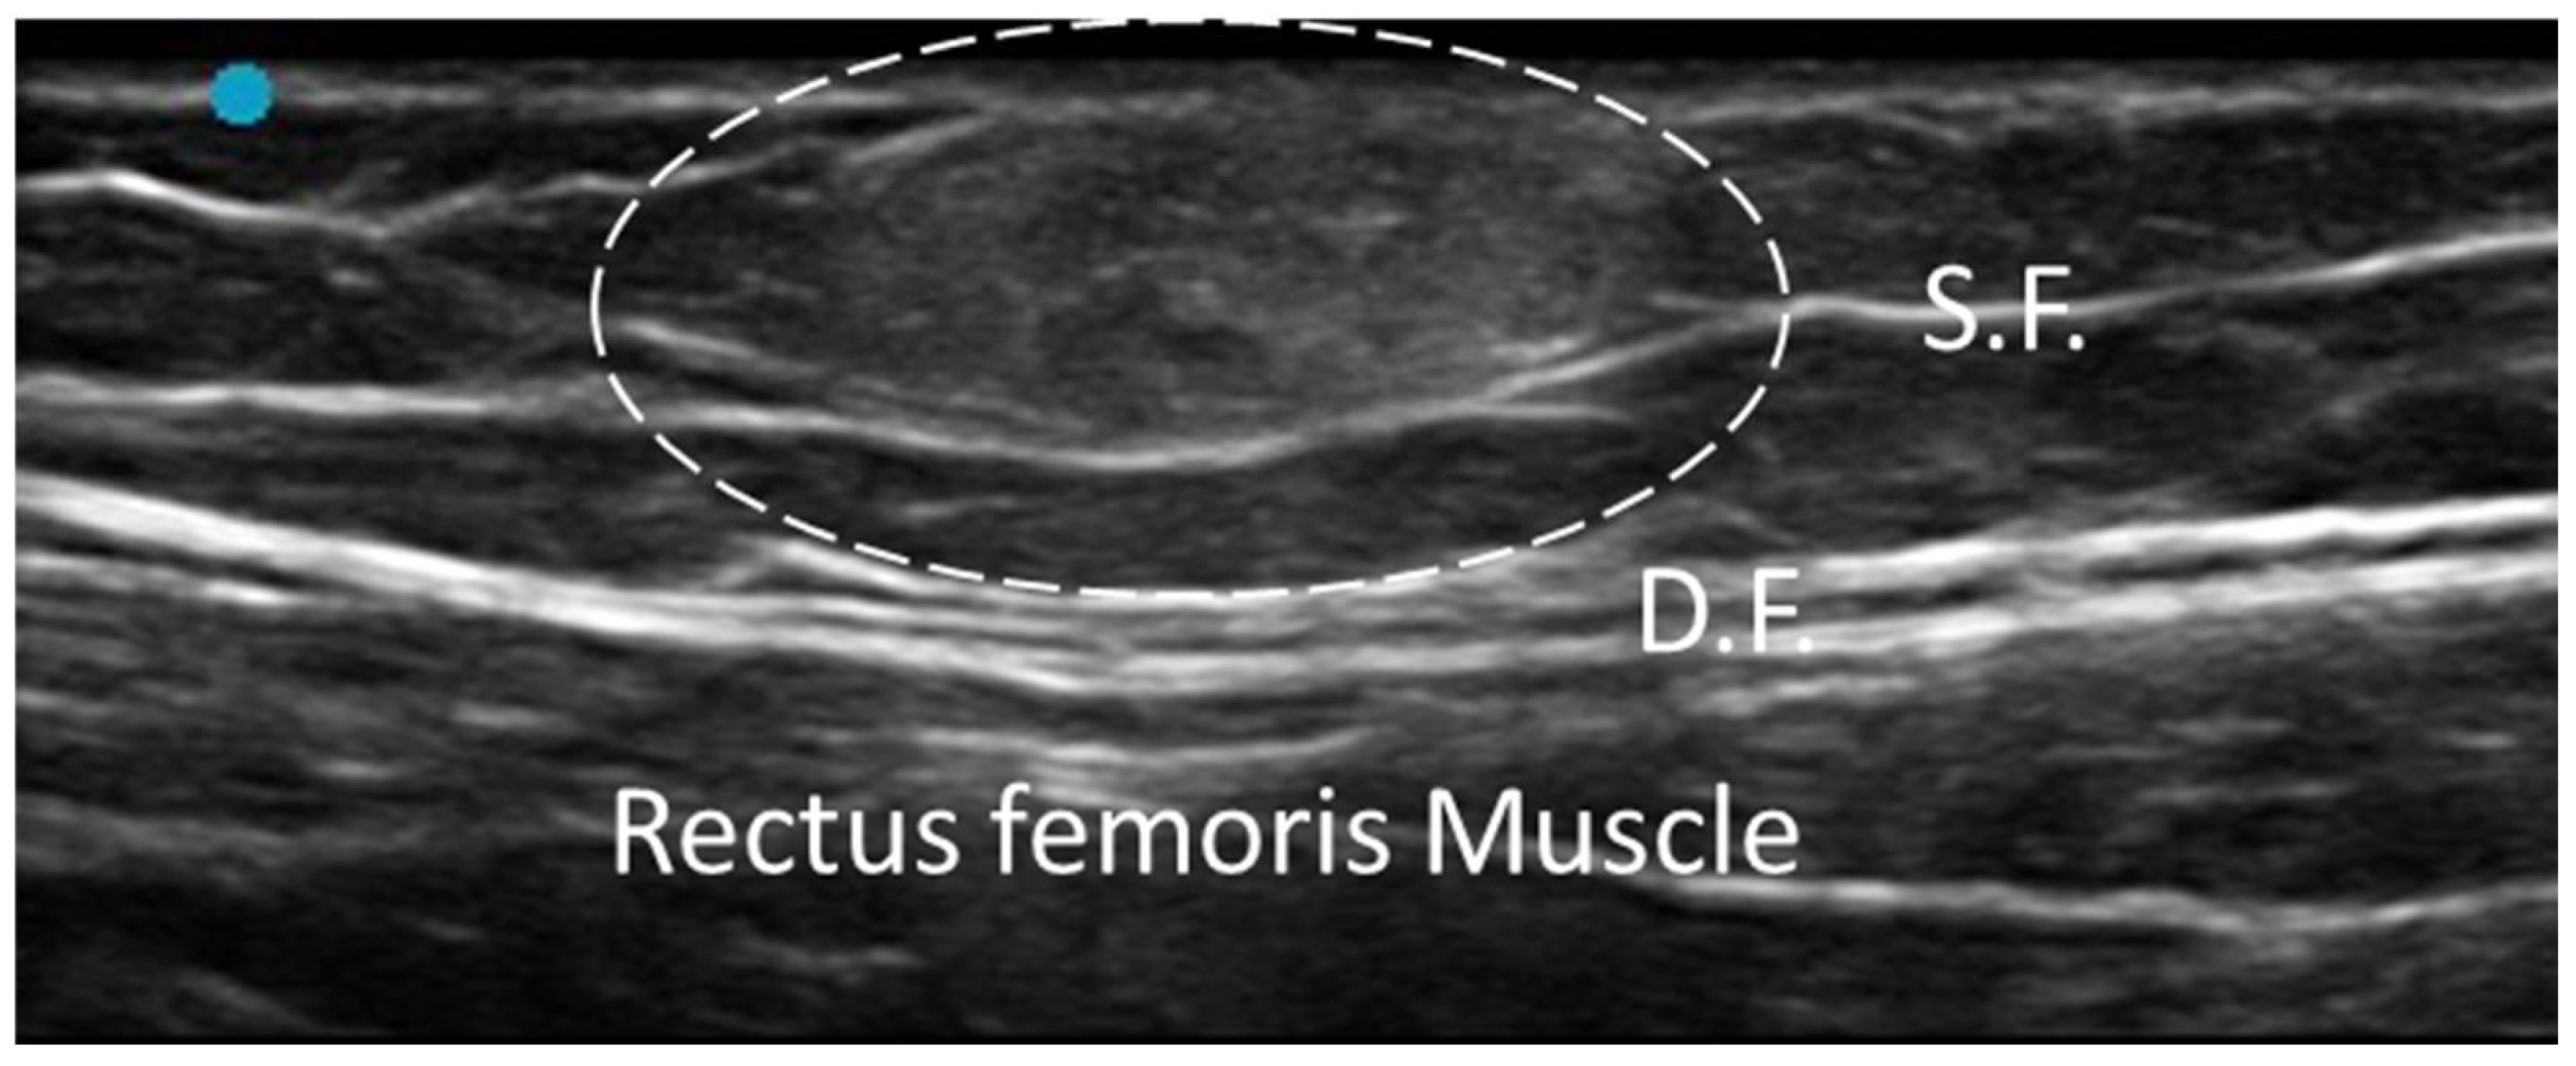

3.5.3. Myofascial Trigger Points